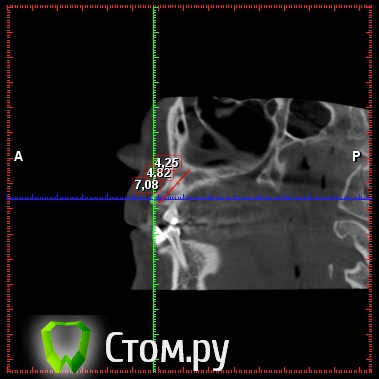

diesel87 Опубликовано 19 декабря, 2013 Поделиться Опубликовано 19 декабря, 2013 Обратилась пациентка, ретенированный 13, располагается горизонтально, брекет систему ставить не хочет, просит удалить этот клык и поставить на его место имплантат, меня интересует вот что, клык то я удалю, что с последующей имплантацией и когда ее провести, просто по кт клык залегает перпендикулярно ось имплантата, прилагаю срезы кт Ссылка на комментарий

diesel87 Опубликовано 19 декабря, 2013 Автор Поделиться Опубликовано 19 декабря, 2013 Меня интересует, как быть с отсутствием кости после удаления, размером с клык, если сразу то есть около 7 мм по вертикали, а потом провал в 4,5 мм и снова кость Ссылка на комментарий

diesel87 Опубликовано 5 января, 2014 Автор Поделиться Опубликовано 5 января, 2014 Планирую удаление, сразу графт и походу может быть винт,хотел по размеру винта проконсультироваться, по КТ расстояние от 14 до 12 зубов 7,2 мм а по вестибулярно-щечному 5,42, с небной стороны не большой провал из-за небного положения клыка, и по длине интересует 12 или 14 ми, планирую 3,8 на 12. Ссылка на комментарий